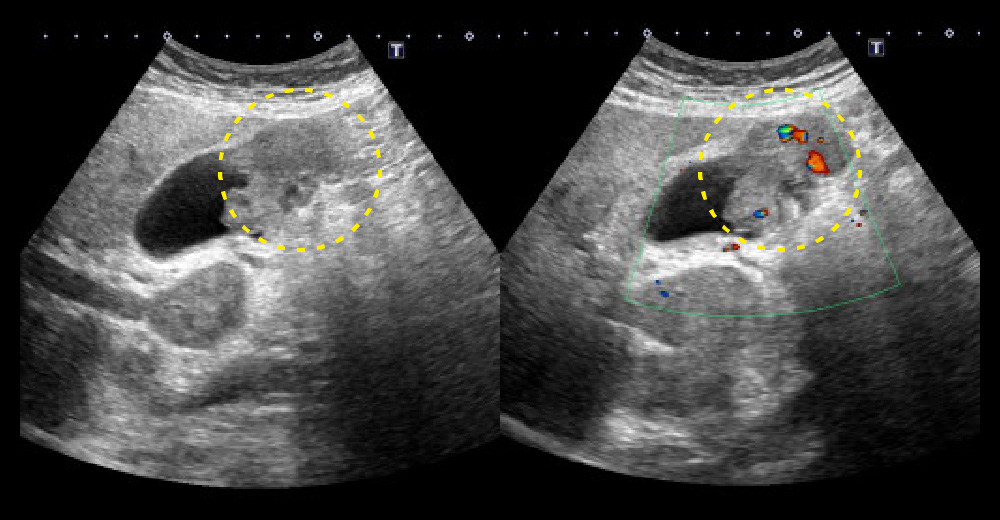

エコー 胆嚢底部を主座とした不整形腫瘤/腫瘤内血流シグナル

左から エコー 胆嚢底部を主座とした不整形腫瘤/腫瘤内血流シグナル